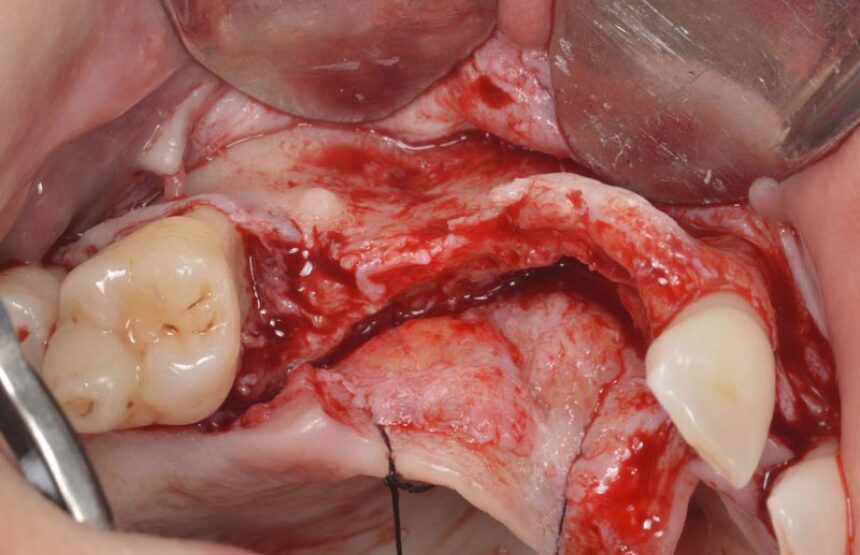

More specifically, ο Dr. Massimo Simion is one of the pioneers of the Guided Bone Regeneration procedure in the area of implant dentistry. Through his thirty-year experience, he will convey his experiences in this area, as well as the secrets of success in cases of extended deficit of the alveolar crest, in both the maxilla and the mandible, and he is going to present the management of various complications that may arise in handling such cases, which is a challenge for clinicians.

Horizontal and Vertical Ridge Augmentation: scientific background - surgical techniques – resorbable and non-resorbable membranes - bone graft harvesting from intra-oral sites – video

Surgical techniques for hard and soft tissue augmentation.

Management of GBR complications.

Diagnosis, prevention and treatment of peri-implantitis